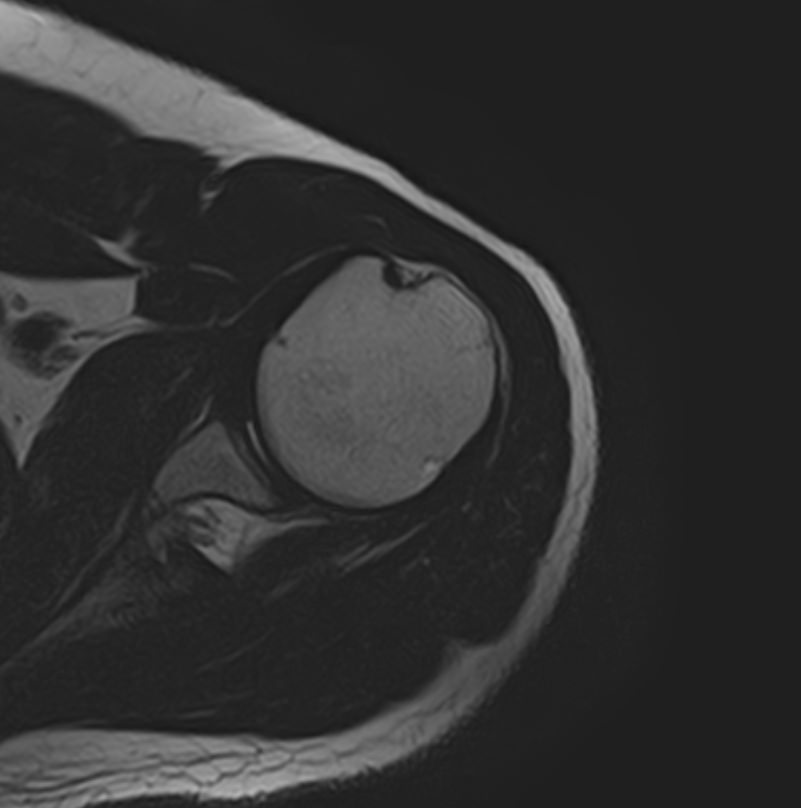

Метод МРТ позволяет оценить состояние всех анатомических областей плечевого сустава,  включая костную структуру, суставную капсулу, полость сустава с выстилающей его синовиальной оболочкой, связки, сухожилия, мышцы и окружающие мягкие ткани.

В клинике «Доступная медицина» исследование проводится на современном высокопольном томографе закрытого типа TOSHIBA VANTAGE TITAN 1,5 Тесла с превосходной  разрешающей способностью, которая обеспечивается высокой индукцией магнитного поля. Аппарат выполняет сканирование послойно в различных плоскостях и на основе этого создает 3D-изображения с высочайшей точностью и достоверностью, что позволяет эффективно ставить диагноз и назначать необходимое лечение.